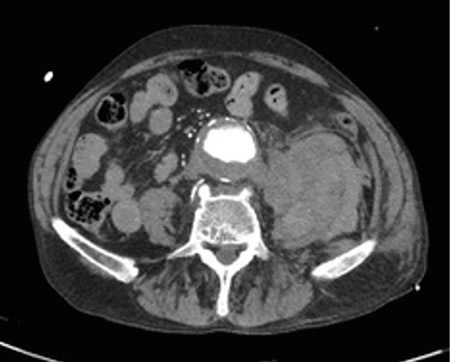

Respecto a las pruebas complementarias, en la analítica sanguínea, se halla una PCR de 39,1 mg/l, leucocitosis de 21.300/mm3, con 88 % de neutrófilos, y una hemoglobina de 10,5 g/dl. En la radiografía pélvica no se evidencian hallazgos patológicos. Debido a la hipotensión, se decide realizar un TC abdominal (Figuras 1 y 2), en el que se objetiva un aneurisma de aorta infrarrenal roto, con diámetro de 50 x 52 x 48 milímetros, a 50 mm de arteria renal derecha y a 65 mm de arteria renal izquierda, craneal a la bifurcación ilíaca. Asimismo, se aprecia un hematoma retroperitoneal en contexto de sangrado en parte posterior de la aorta, que infiltra el músculo psoas ilíaco izquierdo, justificando la clínica de coxalgia con irradiación izquierda. Se contacta con cirugía vascular, interviniéndose de forma urgente, con buena evolución posterior.

Fig. 1. TC coronal de aneurisma de aorta abdominal.

Fig. 2. TC transversal de aneurisma de aorta abdominal.